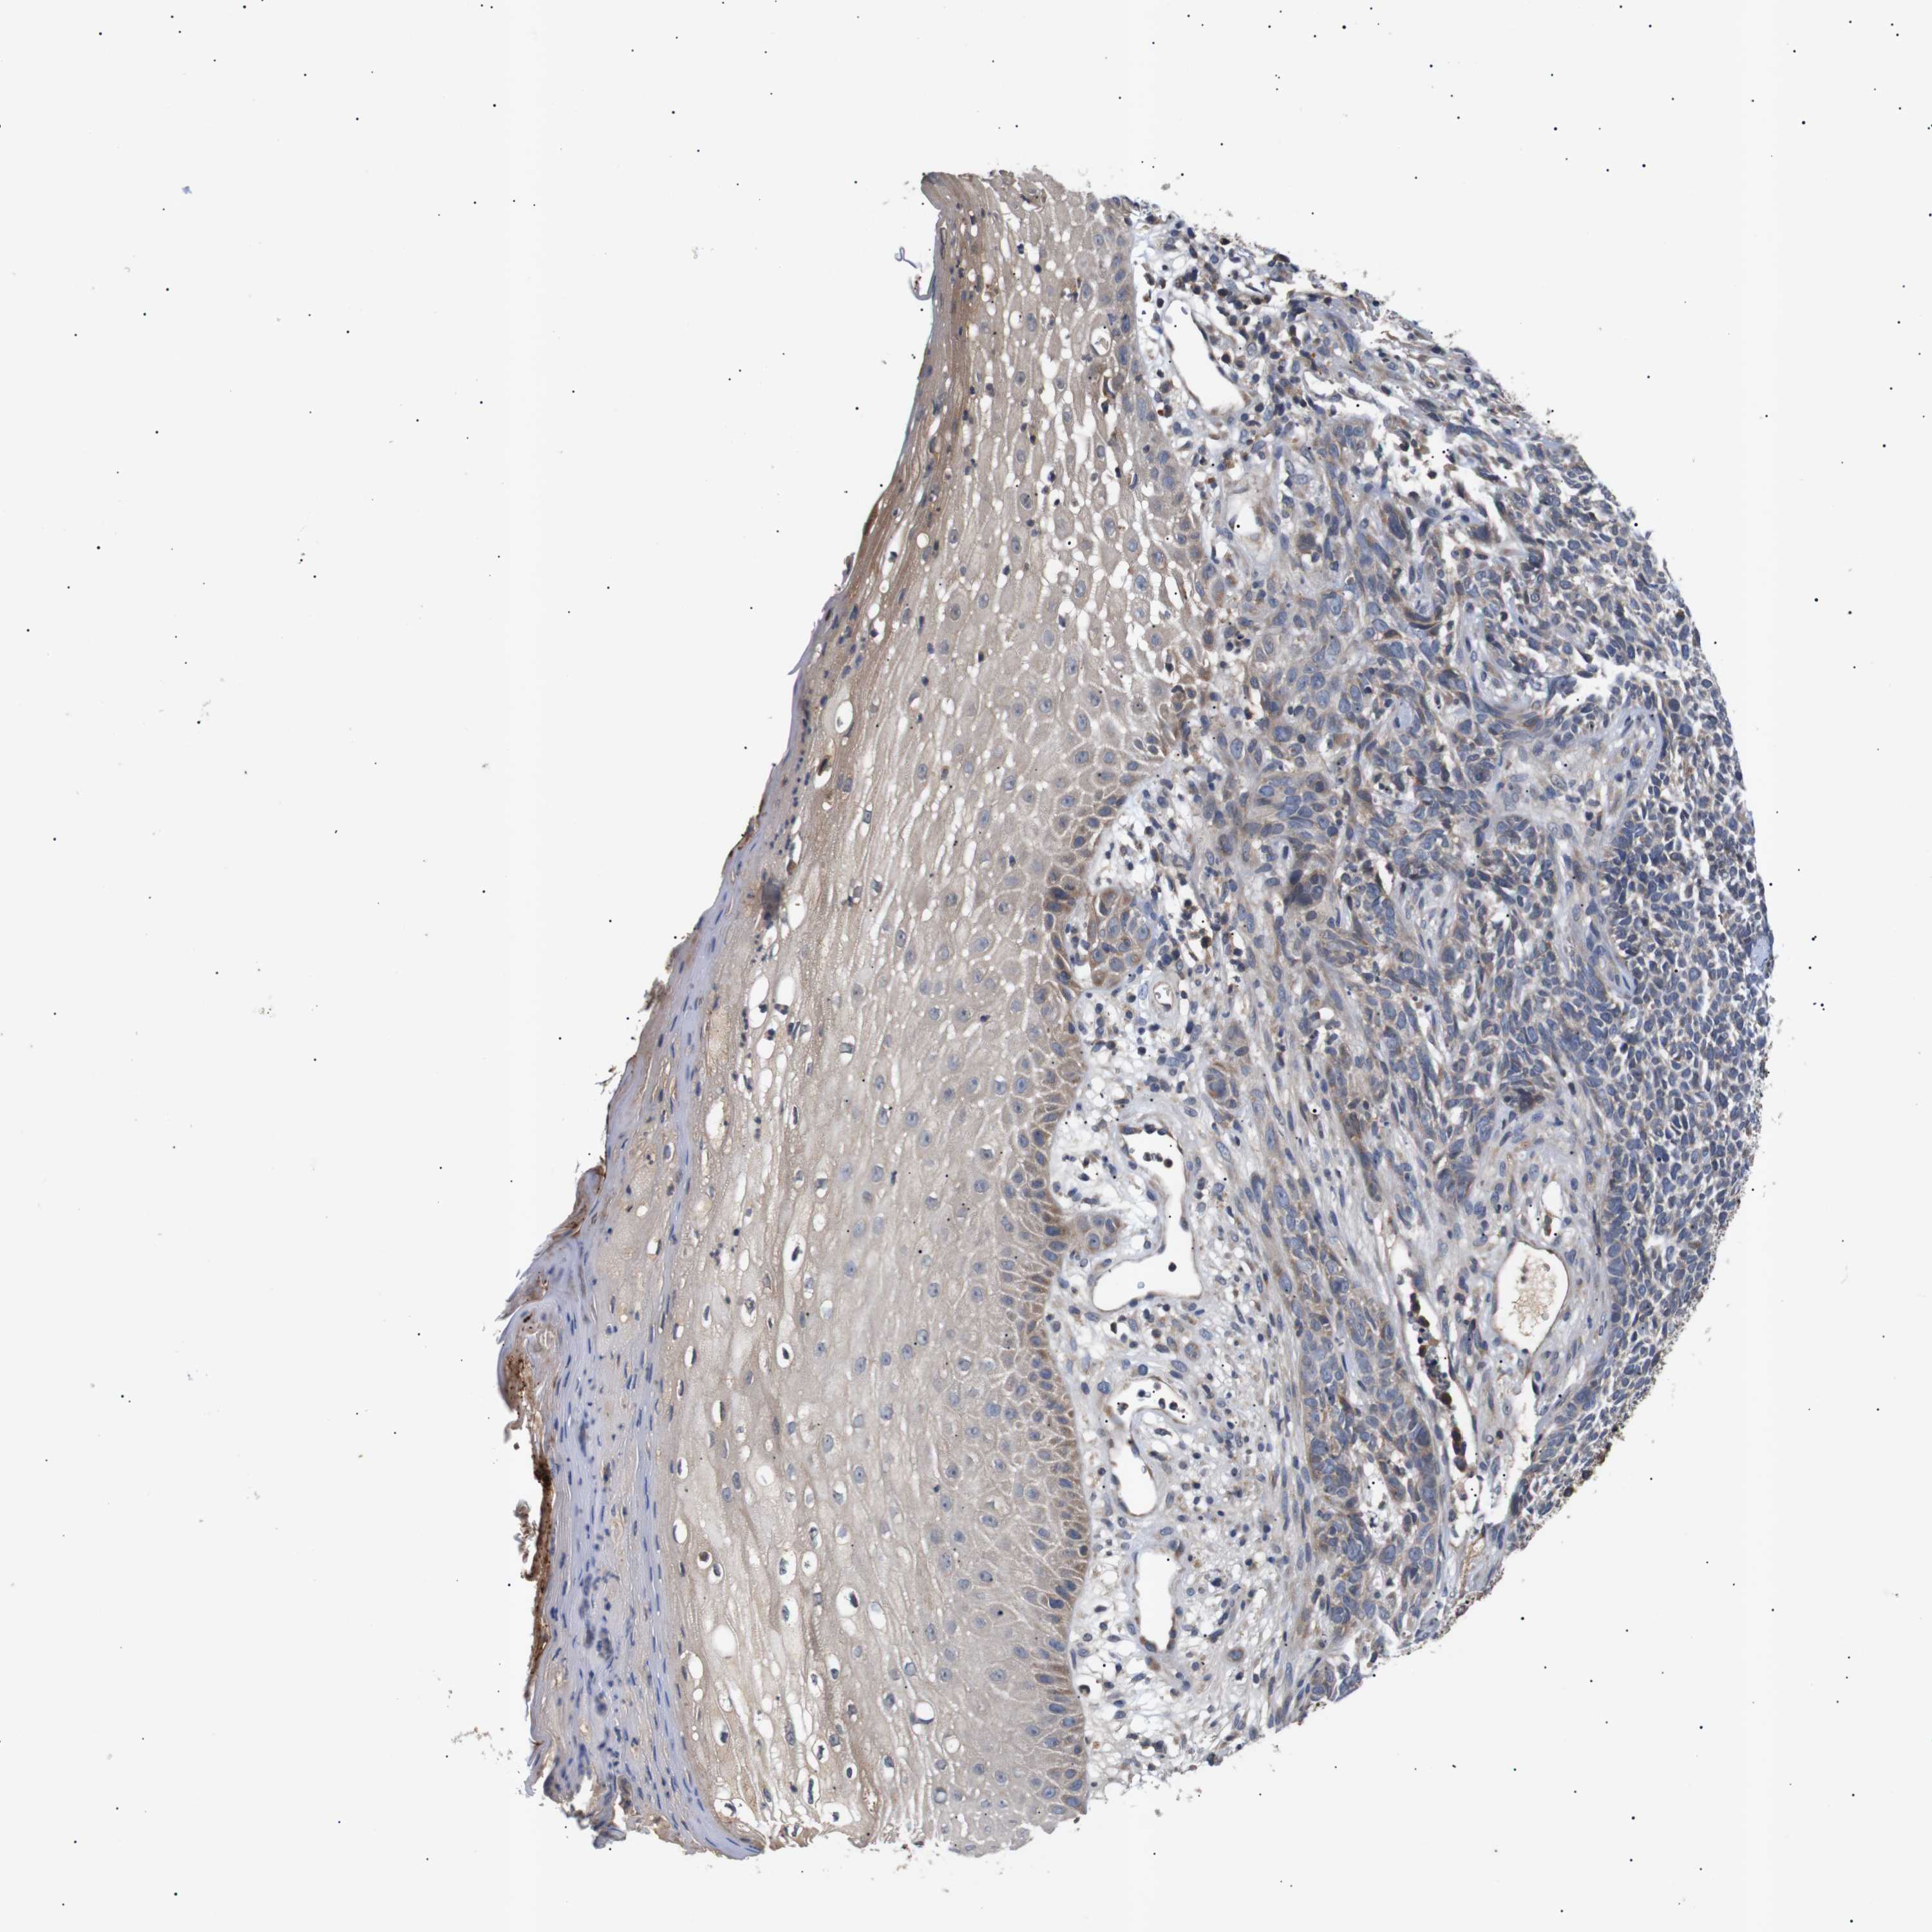

SKIN CANCER - Protein expressioni

A mouse-over function shows sample information and annotation data. Click on an image to view it in a full screen mode. Samples can be filtered based on level of antibody staining by selecting one or several of the following categories: high, medium, low and not detected. The assay and annotation is described here.

Each image is clickable and will lead to virtual microscopy that enables deeper exploration of all samples and also displays staining intensity scores, fraction scores and subcellular localization as well as patient and tissue information for each sample.

Antibody HPA015257

Squamous cell carcinoma in situ, NOS

Squamous cell carcinoma, NOS

Squamous cell carcinoma, metastatic, NOS

Basal cell carcinoma

Adnexal tumor, benign